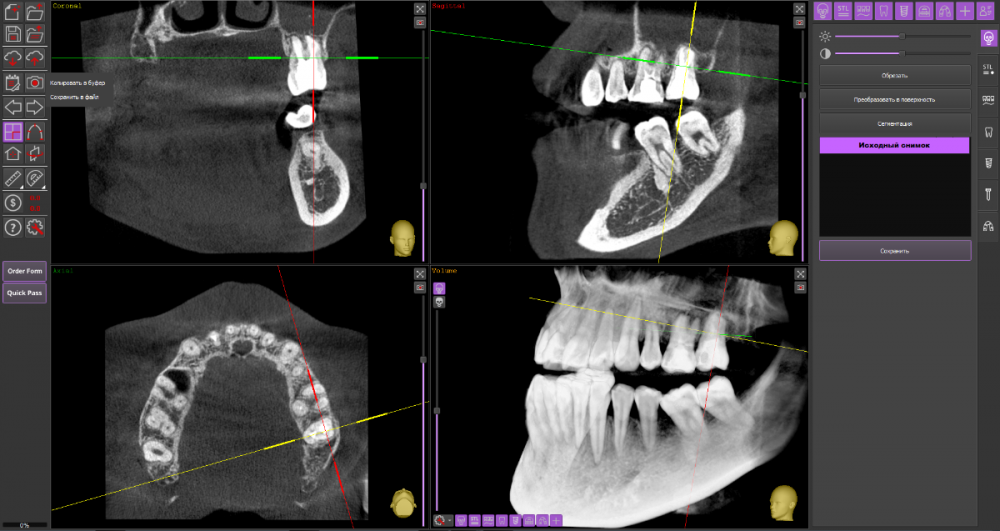

Киста 6,7 слева и гайморит

Гайморит: в начале декабре начала лечение гайморита, сделали прокол, вылился гной пропила антибиотики. ЛОР сказала идти лечить зубы

Зубы: лечение начала в конце декабря. на кт обнаружили кисту над 6,7 зубами слева. 7 зуб заходит в пазуху. Начали лечить 6, сказали что попробуют спасти, заложили лекарство на 2 недели. Также стоял ортодонтический имплантат рядом с 7 зубом, сказали что находится очень близко к корню зуба и пазухе. Имплант удалили.

КТ

Думаю, стоит пока попробовать консервативное лечение у стоматолога-терапевта.

26_1.thumb.png.9a4fd818b43174c9c8d7b0e6cd2bcd15.png